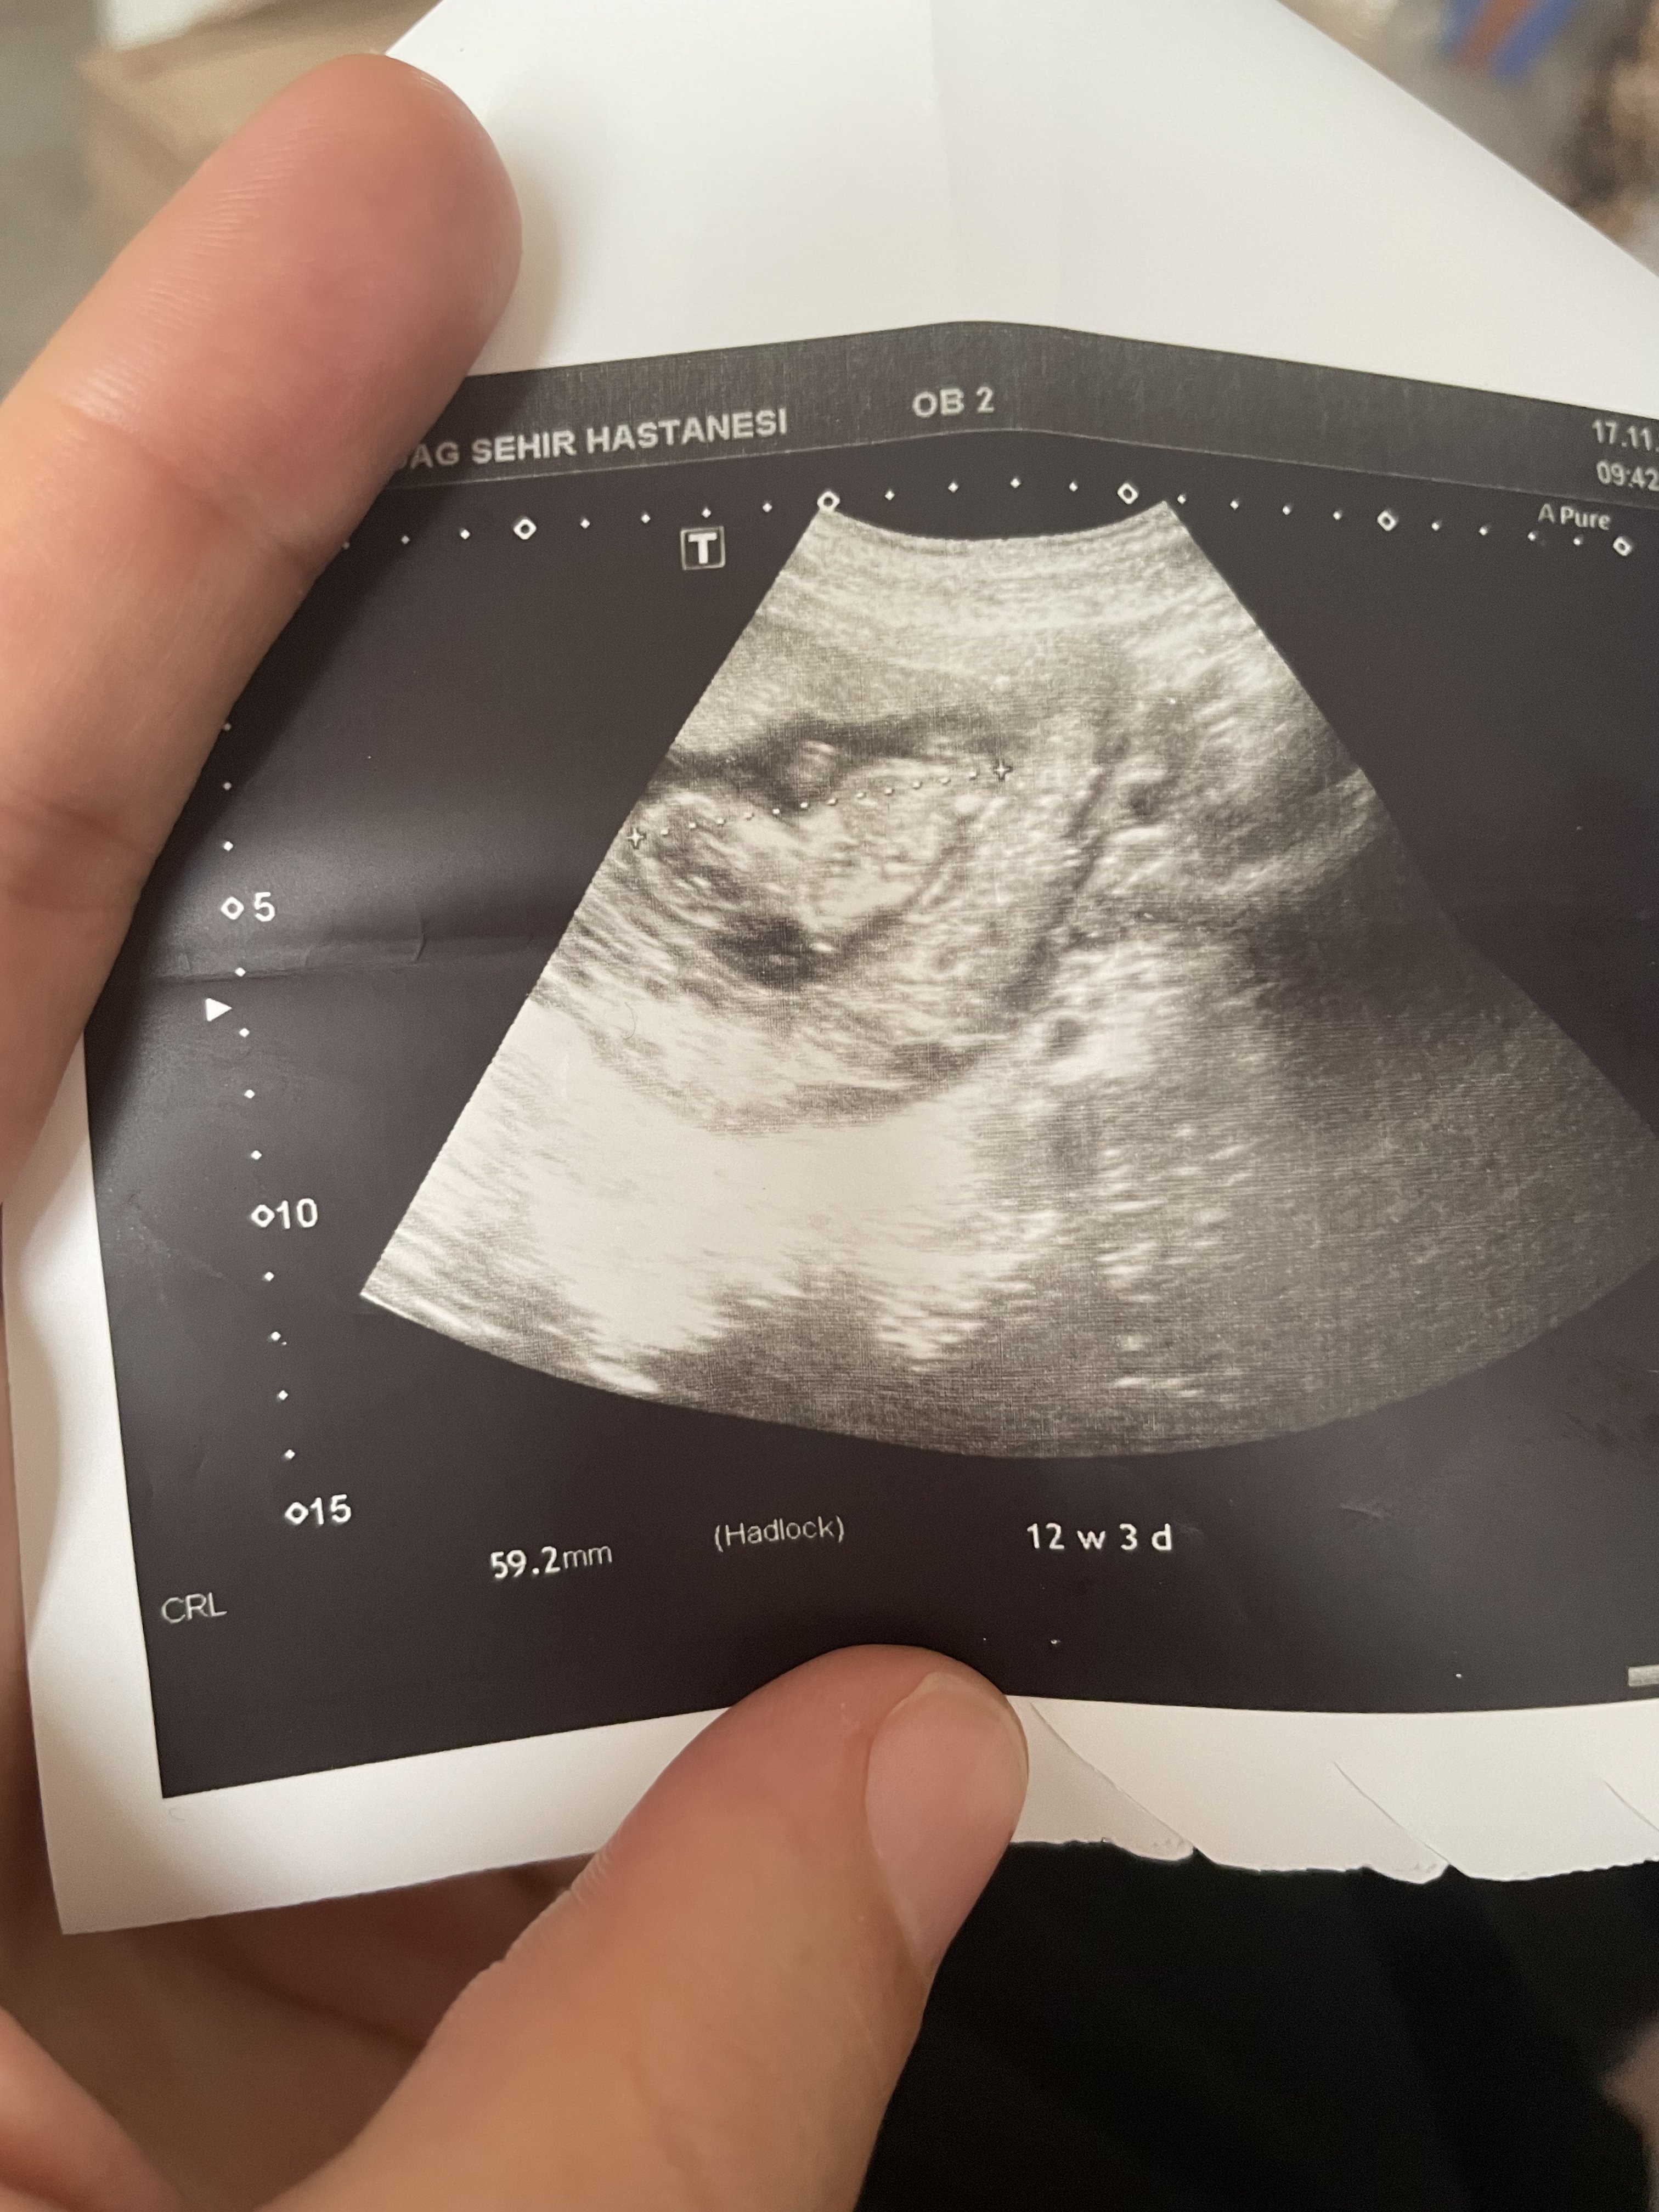

H Hayırlısı Hamiş Melek 18 Kasım 2022 #173 12+3 olduk biz 10+2 de kız demşştiniz fikriniz aynı mı acaba ☺️

SadmiN ♥ Evli Mutlu Çocuklu ♥ Yönetici 20 Kasım 2022 #178 Selamlar bu resim net hayatım kız görünüyor. İnşallah yanılmam 🙂

SadmiN ♥ Evli Mutlu Çocuklu ♥ Yönetici 20 Kasım 2022 #180 Tinimini' Alıntı: Benim mi 😉 Genişletmek için tıkla ... Yok bitanem @gmzgrr arkadaşımızın eklediği resim hayatım seninki net değildi.

Tinimini' Alıntı: Benim mi 😉 Genişletmek için tıkla ... Yok bitanem @gmzgrr arkadaşımızın eklediği resim hayatım seninki net değildi.